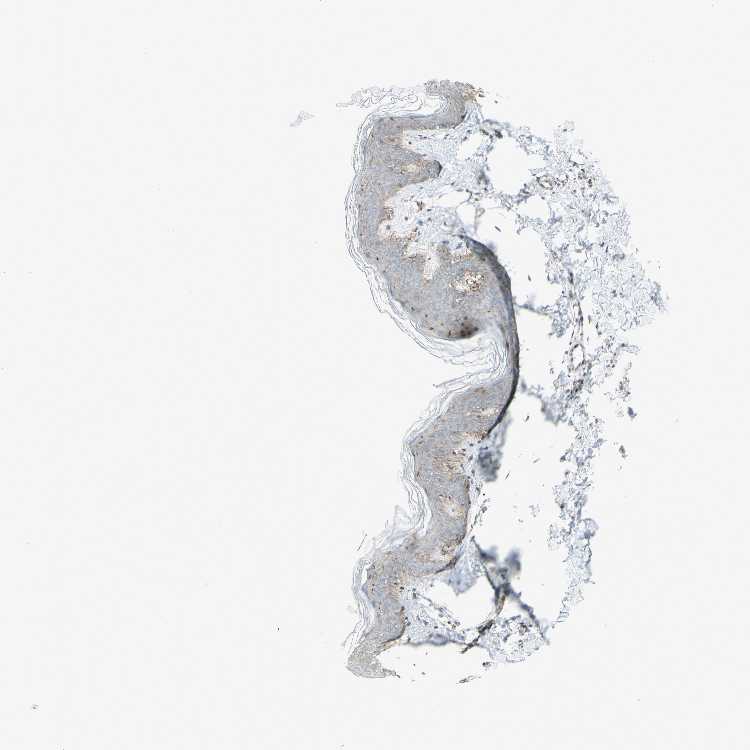

TISSUE PRIMARY DATA SKIN Show tissue menu

Skin

SKIN - Expression summary

SKIN 1 - Antibody stainingi

Antibody staining in the annotated cell types in the current human tissue is reported as not detected, low, medium, or high, based on conventional immunohistochemistry profiling in selected tissues. This score is based on the combination of the staining intensity and fraction of stained cells.

Each image is clickable and will lead to virtual microscopy that enables deeper exploration of all samples and also displays staining intensity scores, fraction scores and subcellular localization as well as patient and tissue information for each sample.